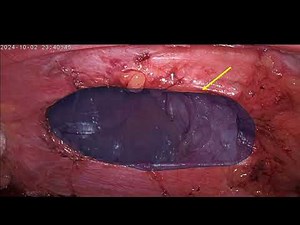

Laparoscopic mesh repair of diaphgragmatic hernia(Morgagni)

…

8.3K views

Dec 5, 2024

YouTube

Rasesh Solanki

Laparoscopic Repair of Incarcerated Morgagni Hernia

463 views

Sep 9, 2023

SAGES - Minimally Invasive Surgery Videos